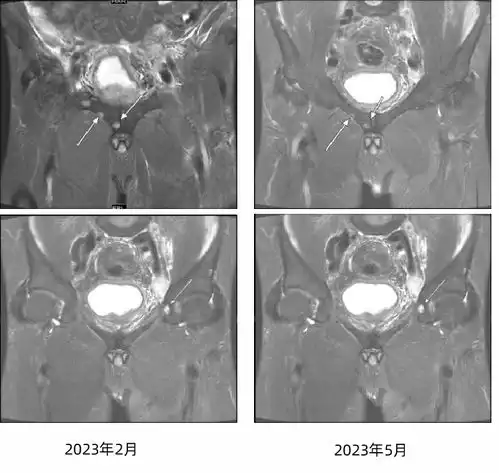

杨彬教授伴骨转移的激素敏感性前列腺癌治疗及骨保护剂应用的临床探索